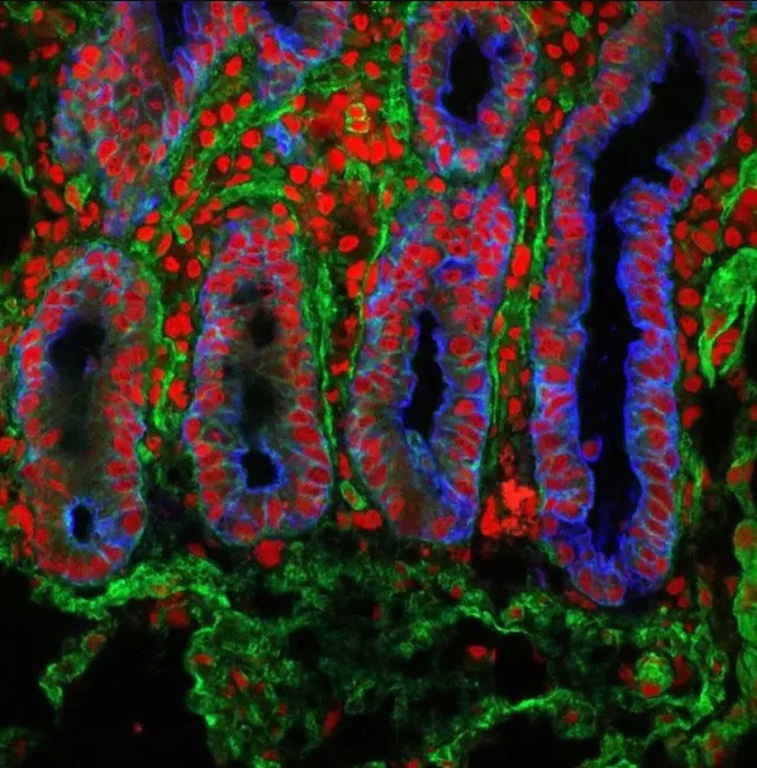

Primer punto, el alto grado de detalle que tienen las fotos. Se nos dificulta concebir un ojo, un óvulo, un pulmón, el iris del ojo, la célula capilar del oído, como unidades separadas y no como partes de un todo.

La representación del iris del ojo no tiene nada que ver con el placer que sentimos cuando (a través de ese iris) observamos algo bello. La representación de la superficie de la lengua no nos remite, no se nos hace parecido, a lo que sentimos cuando degustamos un bocado delicioso. La imágen microscópica de lo que son la ovulación y la fecundación de un óvulo, no alcanza para abarcar los miles de significados que estos procesos pueden tener para cada uno de nosotros. Estas imágenes pueden representarlos perfectamente a nivel biológico pero, queda en evidencia, nuestro cuerpo tiene para nosotros un sentido que excede al biológico.

Ahora, comencemos el recorrido. Disfrutemos de estas imágenes, permitiéndonos experimentar la fascinación, la impresión o la repulsión, sabiendo que, mirado tan de cerca, nuestro cuerpo puede resultarnos más parecido a una obra de arte abstracto que a la experiencia de tener un cuerpo.